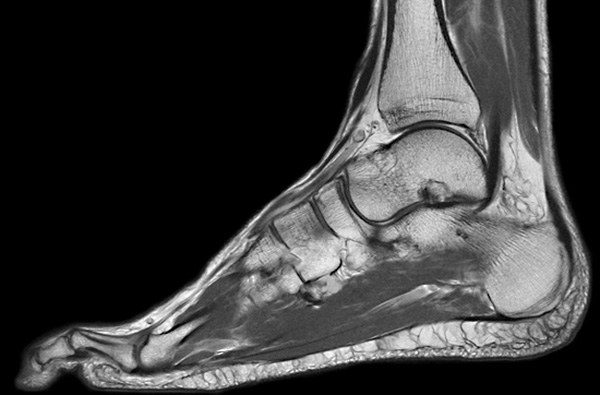

Es el estudio de estructuras anatómicas compuestas por huesos, musculatura, tendones, cartílago etc.

En exploraciones de miembros inferiores, el paciente es colocado en la camilla boca arriba y entran primero los pies, de tal manera que la cabeza queda fuera del gantry, minimizando así la sensación de claustrofobia. Las exploraciones osteoarticulares suelen durar unos 15-20 minutos.

Ejemplos